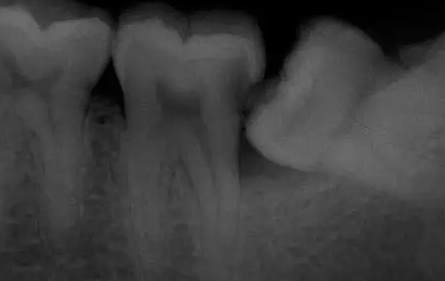

阻生智齿尽头牙图片

由于智齿是最后一颗牙齿,刷牙时不易清理,局部卫生状况较差,因此可以发生牙冠周围牙龈发炎,称之为冠周炎。这是智齿萌出后最易发生的病变。患者如果不及时就诊可以继发间隙感染,导致面部肿痛、张口受限,有些病人还会发热,甚至形成面颊瘘,经久不愈,给患者带来极大痛苦。